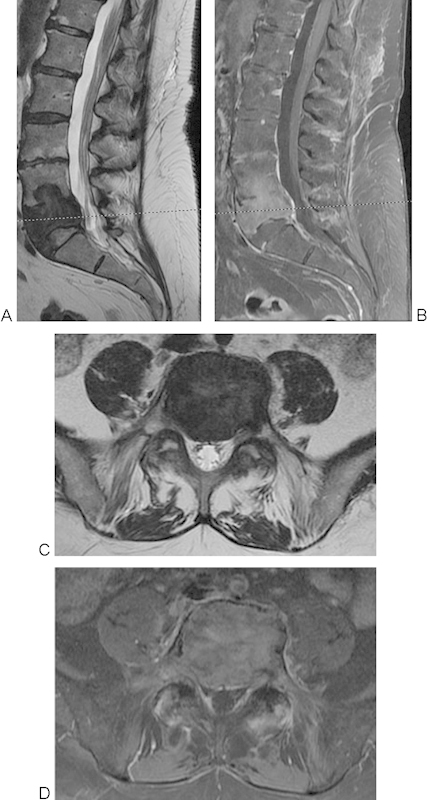

研究设计个案报告及文献回顾。目的:我们在L4和L5行两节段腰椎切除术,以实现巨细胞瘤(GCT)的整体切除和腰骨盆重建。方法一名58岁的女性,有7个月的进行性顽固性背痛和腿部疼痛史,继发于活检证实的L4和L5椎体Enneking III期GCT。患者在两个手术阶段成功接受了L4-L5椎体切除和前后联合入路腰骨盆重建。结果术后并发症包括深部伤口感染和脑脊液漏;然而,在手术清创和长期抗生素治疗后,患者神经功能完好,疼痛最小,随访2年以上无肿瘤复发或器械失效的证据。结论椎体切除术是治疗Enneking III期gct累及下腰椎的一种可行且有效的治疗方法。腰骶交界处是脊柱切除后重建的一个具有挑战性的解剖位置,具有独特的技术考虑。

Study Design Case report and review of the literature. Objective We present the case of a two-level lumbar spondylectomy at L4 and L5 for en bloc resection of a giant cell tumor (GCT) and lumbopelvic reconstruction. Methods A 58-year-old woman presented with a 7-month history of progressive intractable back and leg pain secondary to a biopsy-proven Enneking stage III GCT of the L4 and L5 vertebrae. The patient underwent a successful L4-L5 spondylectomy and lumbopelvic reconstruction using a combined posterior and anterior approach over two operative stages. Results Postoperative complications included a deep wound infection and a cerebrospinal fluid leak; however, following surgical debridement and long-term antibiotic treatment, the patient was neurologically intact with minimal pain and there was no evidence of tumor recurrence or instrumentation failure at more than 2 years of follow-up. Conclusion Spondylectomy that achieves en bloc resection is a viable and effective treatment option that can be curative for Enneking stage III GCTs involving the lower lumbar spine. The lumbosacral junction represents a challenging anatomic location for spinal reconstruction after spondylectomy with unique technical considerations.